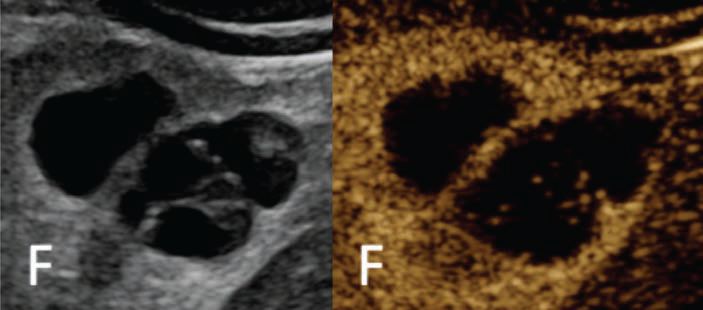

A multidisciplinary Expert Panel provides unified guidance on imaging, diagnosis, and management of pediatric renal cysts; reviewing roles of US, CT, MRI, and incorporating the modified Bosniak classification to clarify challenging cases. www.ajronline.org/doi/10.2214/...